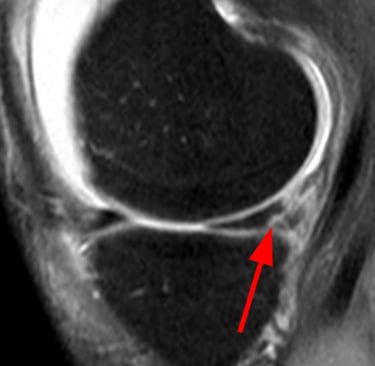

Tanı

Fizik muayene (McMurray, Thessaly testleri)

MR görüntüleme ile kesin tanı